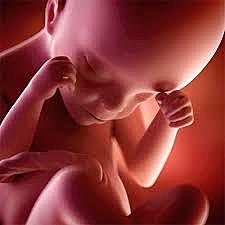

• Semana 20

Semana 20

el lanugo cubre todo el cuerpo

aparecen las cejas y las pestañas

aparecen las uñas en pies y manos

el bebé es más activo con mayor desarrollo muscular

la madre puede sentir al bebé moviéndose

los latidos cardíacos fetales se pueden escuchar con un estetoscopio